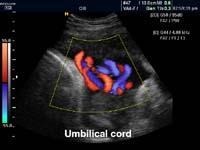

由於胎兒在羊水中生存,超聲影像表面對比強烈,幾乎所有胎兒都可以做出三維表面圖像,可以準確觀察胎兒面部、四肢、胸腹、脊柱。因此可以採用超聲檢查觀察、判斷臍帶在宮腔內的走向及其與胎兒的關係。

臍帶真結在產前難以發現,多數在分娩後確診。三維超聲顯象即3D超聲有時可幫助判斷臍帶在宮腔內的走向及其與胎兒的關係,對臍帶打結有一定準確的診斷率。